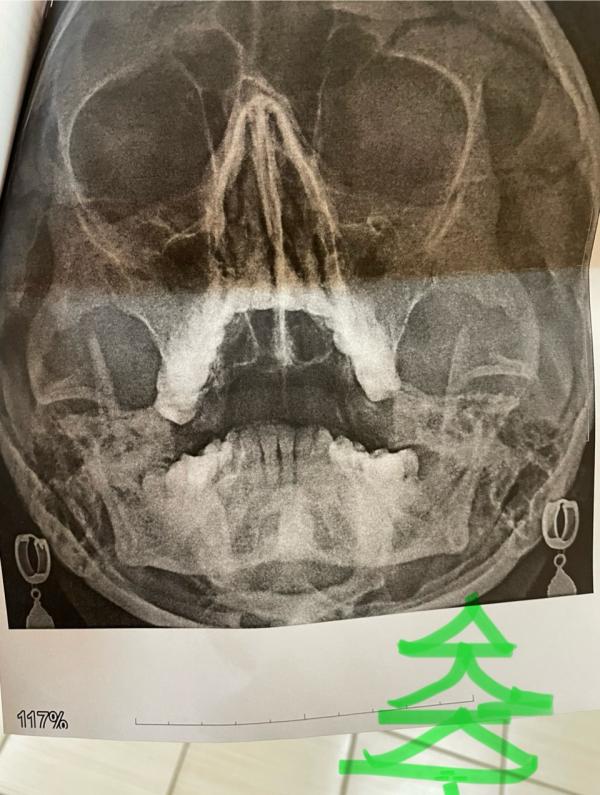

Для страдающих от гайморита и про красоту лица.

Я часто читаю, что многие страдают гайморитами. Помните мой череп с сережками? Этой зимой я писала о том, что у меня было осложнение.

Сама я думала, что это вовсе не мое заболевание. Пока в послековидные времена что то сдвинулось, и я тоже познакомилась с этой неприятностью. Но я к счастью обошлась без антибиотиков и без проколов.